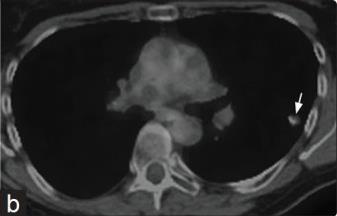

女性,61岁,无吸烟史。

肺CT平扫显示多个双侧分叶状大小不等的肺结节,许多伴有粗大的钙化。最大的结节在左上叶约14 mm,与之前的CT相比,无增大。